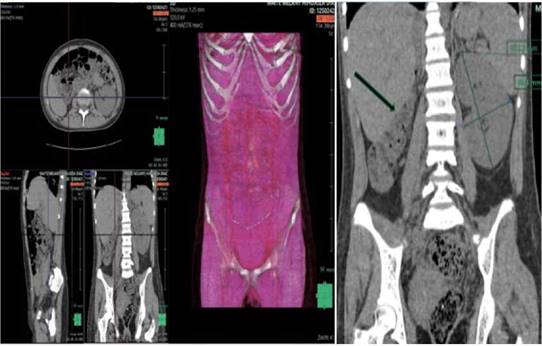

Figura 3: a)Tomografía Computada de abdomen simple en proyecciones axial, sagital, coronal y reconstrucción volumétrica donde se corrobora la agenesia renal derecha con riñón izquierdo compensatorio incrementado de morfología en sus diámetros mayores en relación a monoreno. En cavidad pélvica se observa útero incrementado de tamaño con contenido hipodenso en cavidad endometrial a predominio derecho en relación a hematocolpos. b) Tomografía de abdomen simple en plano coronal donde se observa agenesia renal derecha con hipertrofia fisiológica compensadora del riñón izquierdo incrementado de morfología en sus diámetros longitudinal y anteroposterior mide 122,3 x 68,4mm. en relación a monorreno

Fuente: Hospital Roberto Galindo Teran, Pando-Cobija